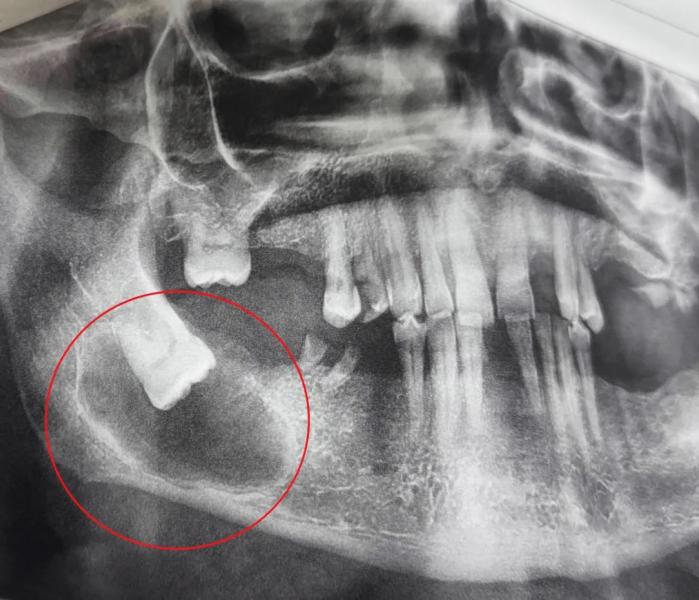

В областную стоматологическую поликлинику обратился 65-летний мужчина с жалобами на ноющие боли в нижней челюсти справа, чувство распирания и асимметрию лица. Врачи обнаружили ретинированный зуб мудрости, расположенный горизонтально, и фолликулярную кисту вокруг него.

Под местной анестезией стоматолог-хирург Анастасия Асеева провела операцию. Сделав разрез и отслоив слизисто-надкостничный лоскут, врач обнажил истончённую кость, создал отверстия и удалил проблемный зуб. Затем специалист полностью удалил оболочки кисты и выскоблил патологические ткани.